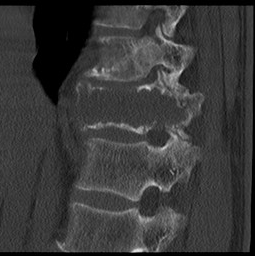

经过慎重考虑,老李决定返乡,并慕名来到我院就诊。脊柱外三科主任陈海龙看到老李的脊柱DR片后,顿感情况不妙,胸11椎体高度降低,椎体骨质及右侧附件结构严重破坏,幸运的是老李目前没有神经损伤症状,否则严重的话可造成双下肢截瘫。陈主任安排医师为老李紧急办理了住院手续,一边叮嘱他绝对卧床,一边加快各项相关检查。结合他的CT及MRI等影像资料显示,结果不过容乐观,不出所料,胸11肿瘤毫无疑问,而后穿刺活检的病理结果再次证实了医生的判断:骨巨细胞瘤。但幸运的是,经过全面彻底排查,未见肿瘤转移,那么此时此刻对老李来讲,完整彻底地切除肿瘤,是最优的选择。